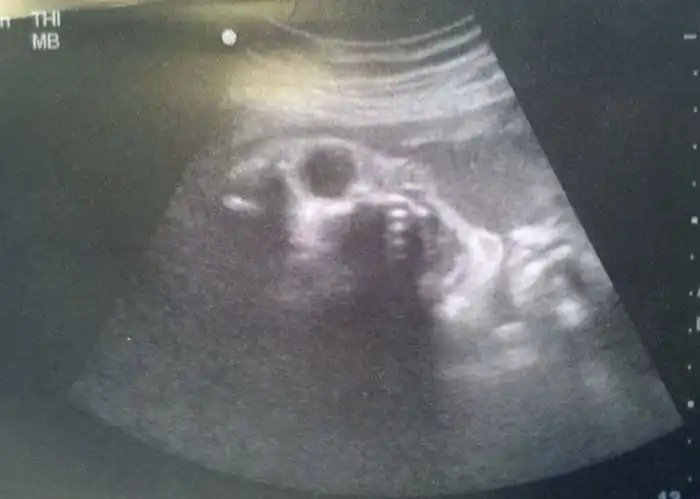

На экранах аппаратов УЗИ дети, находящиеся в утробе матери, выглядят далеко не такими милыми и симпатичными, какими они оказываются после своего рождения.